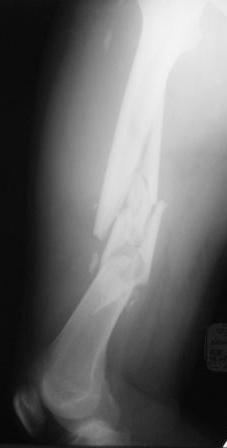

[Ortho] Нужен совет по тактике лечения многооскольчатого перелома бедра

Выбор на пластине основан на том, что проксимальный отломок не цельный, по рентгенограмме видно, что в нём практически до малого вертела имеется осколок. Поэтому у меня опасения, что фиксация внутрикостного стержня в проксимальном отломке не будет достаточно стабильной.